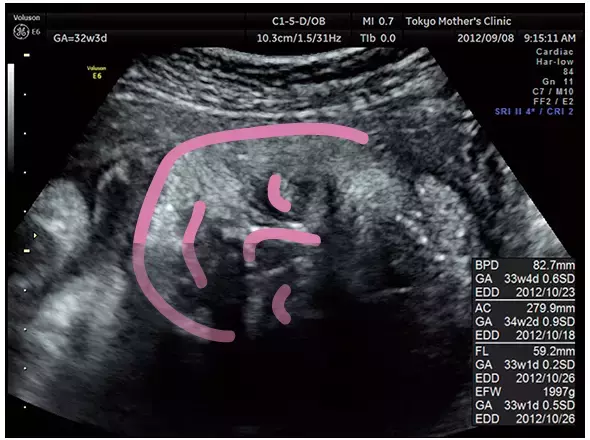

妊娠9ヶ月のエコー(超音波)写真

顔のどアップ画像。

ぷっくりしたほっぺたがかわいらしい。

写真提供:東京マザーズクリニック